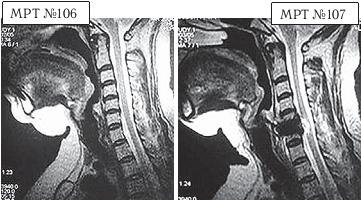

Вот ещё трагический случай во время проведения необоснованной операции.

На МРТ № 106 состояние шейного отдела пациентки до операции. Наблюдается сглаженность физиологического лордоза, ликворные пути свободны, компенсированные протрузии межпозвонковых дисков в сегментах СIII—СIV

На МРТ № 107 состояние шейного отдела той же пациентки после дискэктомии с межтеловым спондилодезом в сегменте CV—CVI, кроме того наблюдается травма спинного мозга на данном уровне хирургической фрезой.

Если до операции у данной пациентки были незначительные вертебробазилярные нарушения, то после… Травма спинного мозга хирургической фрезой — это, конечно, трагическая случайность. Ведь от ошибок никто не застрахован и добросовестный врач никогда не даст гарантии на положительный исход любого вида лечения. Но в данном случае проведение самой операции было абсолютно необоснованным, фактически она превратила нормального человека в инвалида.